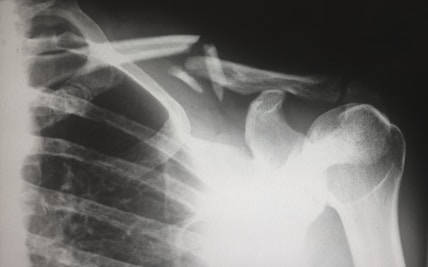

Accidents of any kind—whether from a car crash, slip & fall, workplace incident, or other personal injury—can leave you overwhelmed with medical needs, legal questions, and financial stress. Care Connect is here to step in. Our team links you with trusted doctors who understand your injuries and experienced attorneys who can protect your rights and guide your claim. We focus on coordinating your care and legal support so you can focus on healing, while we help manage the rest.